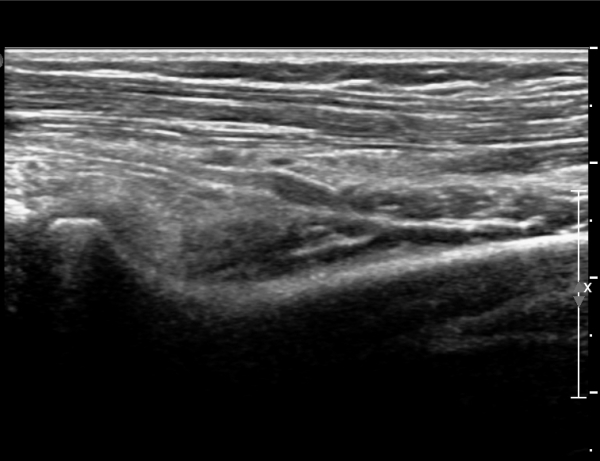

ÃÊÀ½ÆÄ °Ë»ç

¼ÒµÎ(capitulum) À§Ä¡¿¡¼­ Èİñ°£½Å°æ Ⱦ´Ü¸é°Ë»ç»ó Èİñ°£½Å°æÀÌ Àú¿¡ÄÚ ÀÛÀº ¿øÇüÀ¸·Î

°üÂûµÈ´Ù(»çÁø 1)